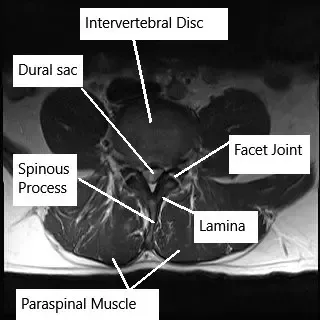

How the Body Part Normally Works? (Relevant Anatomy)

The lumbar spine consists of five vertebrae (L1-L5) separated by intervertebral discs. These discs act as shock absorbers and allow for flexibility and movement of the spine. The spinal cord runs through the spinal canal, and nerves branch out through openings between the vertebrae. These spinal nerves control the sensation and movement of the lower body, including the legs, feet, and pelvic organs. When a disc herniates, it can compress these nerves, leading to symptoms such as pain, numbness, and weakness.

- MRI (Magnetic Resonance Imaging): The most effective tool for visualizing herniated discs and nerve compression.